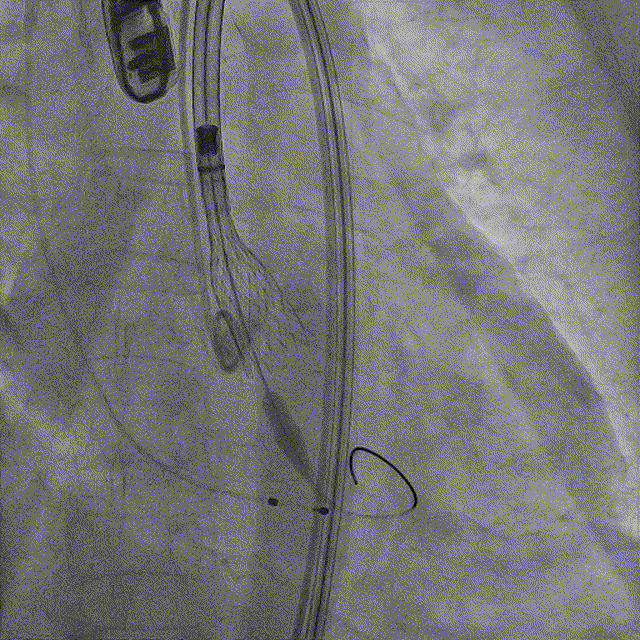

瓣膜定位和初始释放:采用美敦力标准化流程,应用Cusp overlap 技术,在模拟的左右窦重合的释放角度下将标记带调整到猪尾的中间开始释放

瓣膜释放到2/3:瓣膜缓慢释放到1/3时开始快速起搏,然后释放速度稍快一些直到2/3处(此处有触觉提示)。

瓣膜释放到80%:从2/3处开始缓慢释放到80%(即hat marker 标记带和上方黑色标记即将重合),然后进行各项(深度、流速、压差、反流等)评估。

最后释放:转至三窦共面视角,调整LAO至瓣膜流入端无视差,再次评估确认后从无冠窦撤出猪尾导管,回拉导丝释放张力并做最后释放